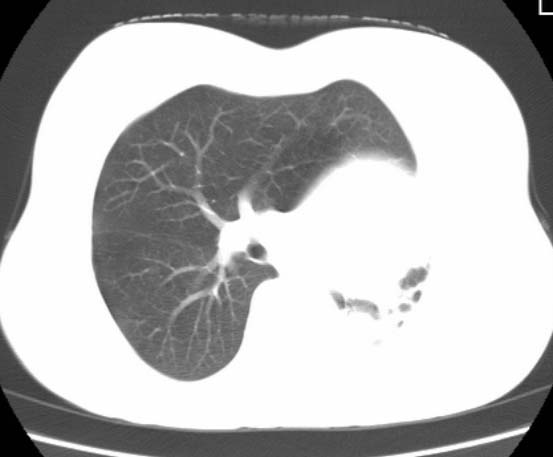

女  20岁。一月前咳血,诊“肺结核”抗痨治疗一月后,咳血停止,现复查。病人精神好。前后ct片对比未见明显变化。既往体检“正常”

1)考虑左肺结核并肺不张、支气管扩张。2)纵隔疝。

以前体检正常只能考虑左肺结核并肺不张、支气管扩张。2)纵隔疝。

考虑左肺结核,左肺毁损,纵膈左偏,既往体检正常不可靠,tb一个月也不会这个样子的,有钙化,应该病程较长,冰冻三尺非一日之寒!

左肺发育不全。

考虑左肺结核,左肺毁损,纵膈左偏,既往体检正常不可靠,tb一个月也不会这个样子的,有钙化,应该病程较长,冰冻三尺非一日之寒

结核,左肺毁损。